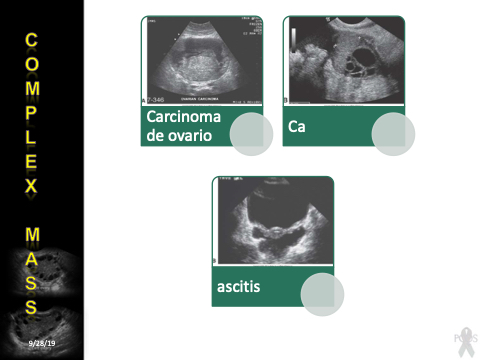

Carcinoma de ovario

Ca

ascitis